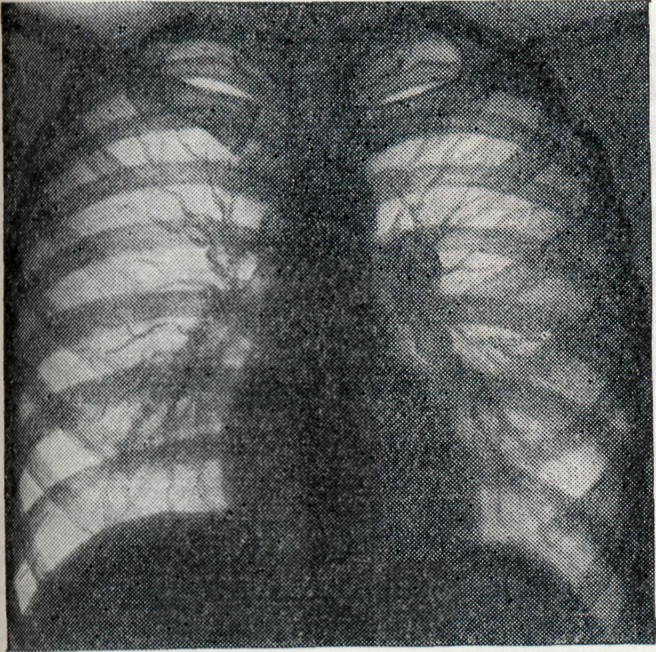

Однако широкое применение рентгенологического исследования больных Б. показало, что и в фазах генерализации инфекции, и в латентном периоде встречаются также бруцеллезный внутригрудной лимфаденит (рисунок 5 и 6), бронхопневмонии и плевриты бруцеллезного происхождения.

Рис. 5.

Легкие здорового человека.